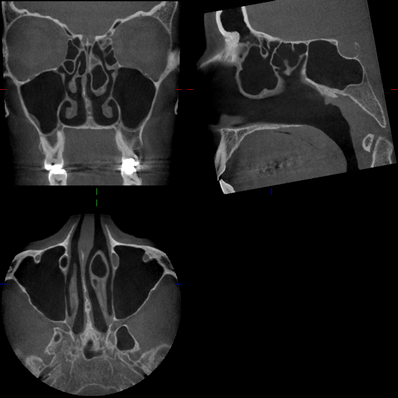

Bilder NNH

Kuhn'sche Zelle Mukozele SH Knochenneubildung Stirnhöhle sagittal Concha bullosa radikuläre Zyste